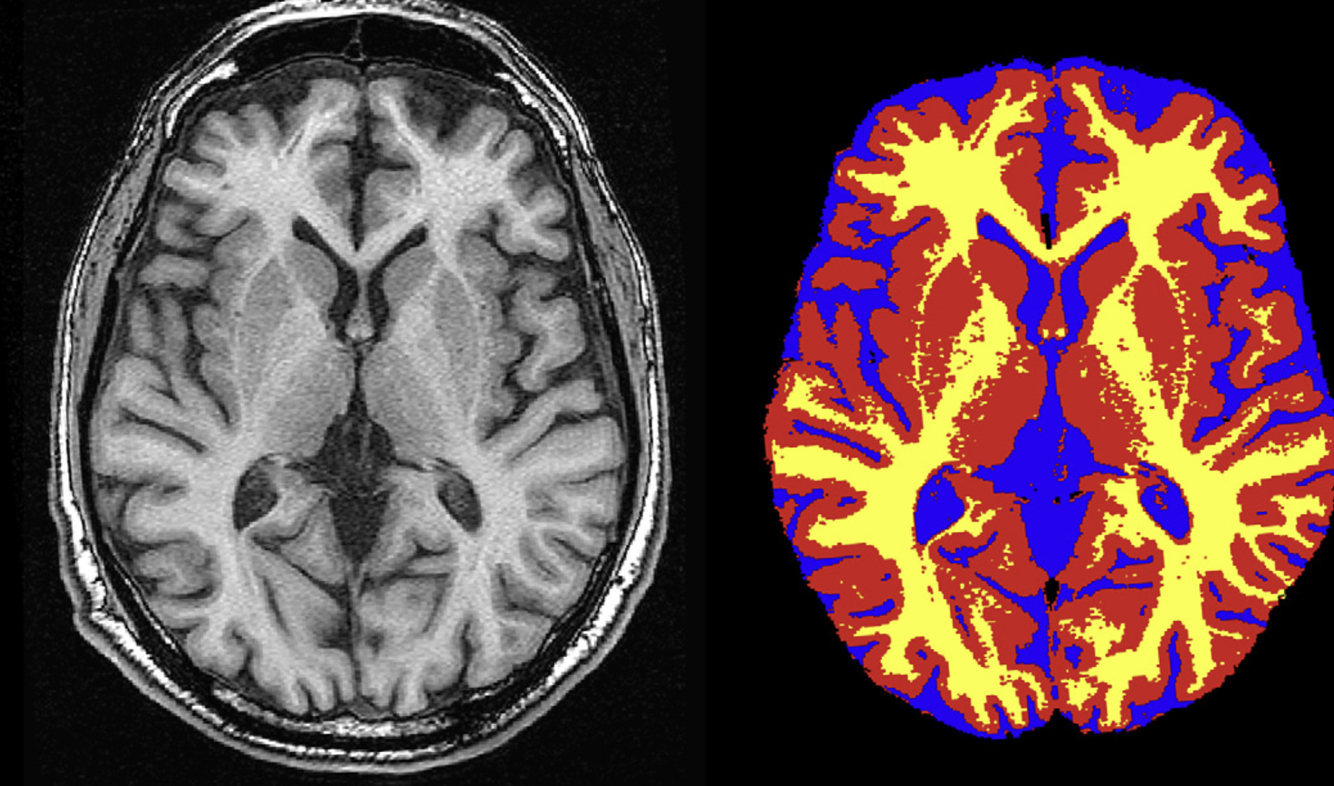

Structural NeuroImaging

Structural neuroimaging modalities (particularly MRI-based approaches) have been instrumental in characterizing changes in brain regions implicated in the processing of non-visual sensory information such as hearing, touch, smell, and memory. These structural changes appear related to use dependency plasticity.

Neuroimaging includes the use of various techniques to either directly or indirectly image the structure or function of the brain. Structural neuroimaging deals with the structure of the brain (e.g. shows contrast between different tissues: cerebrospinal fluid, grey matter, white matter